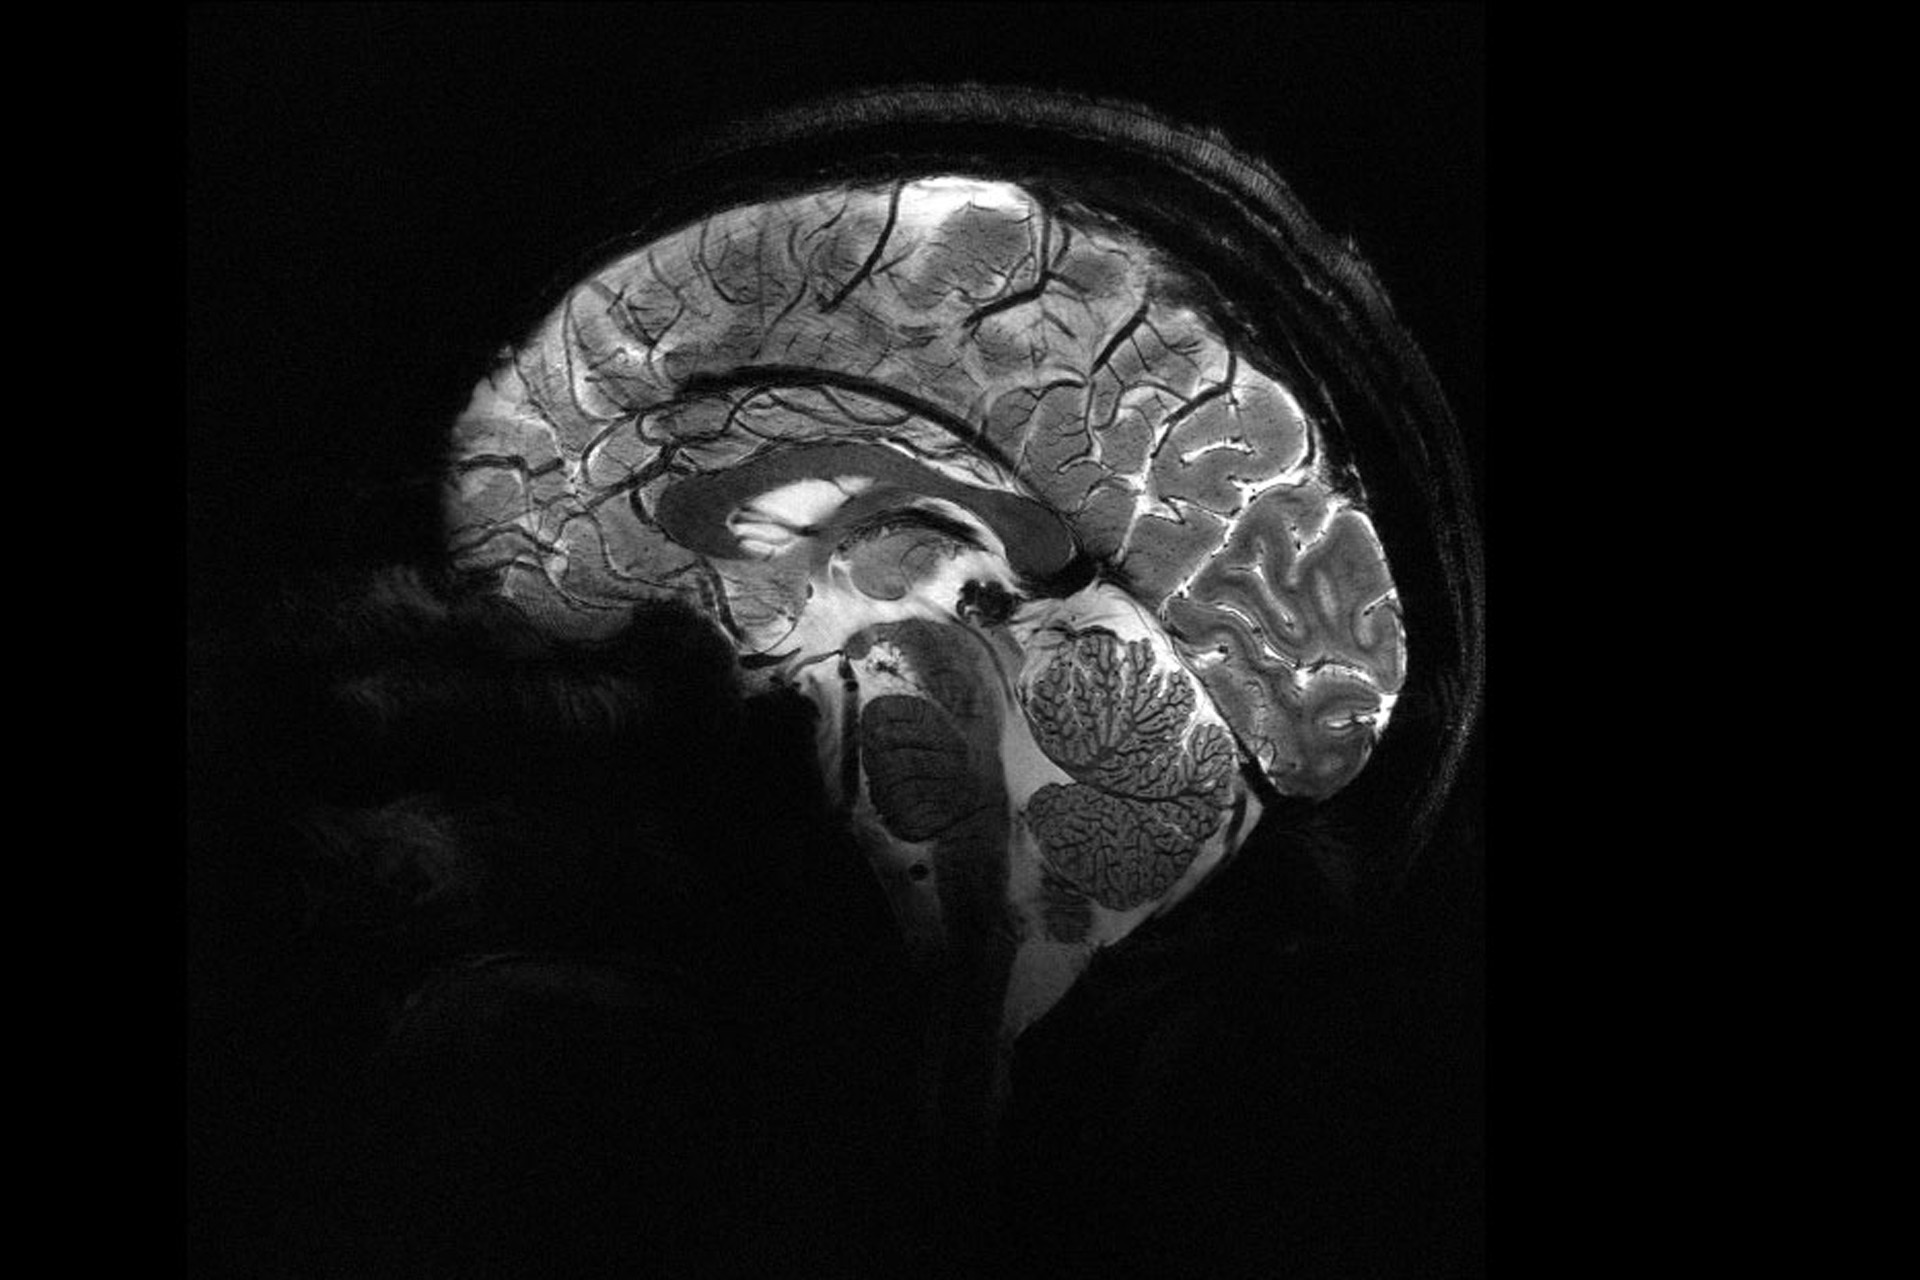

نشرت هيئة الطاقة الذريّة في فرنسا صورة هي الأدق على الإطلاق لدماغ إنسان بعد تلقيهم الضوء الأخضر لاستخدام أقوى جهاز تصوير بالرنين المغناطيسي.

ويقول الفيزيائي ألكسندر فيغنود إنّهم تمكنوا من التوصّل إلى درجة عالية من الدقة لم تتحقق من ذي قبل. وتصل شدّة المجال المغناطيسي الذي ينشئه الجهاز نحو 11.7 تسلا، وتتيح هذه القوّة للجهاز إجراء عمليات المسح بدقة أكبر بعشر مرّات مقارنة بأجهزة التصوير بالرنين المغناطيسي النموذجية في المستشفيات والتي لا تتجاوز قوّتها عادةً 3 تسلا.

ومن خلال مقارنة عدّة صور بين تلك التي التُقطت بالجهاز الحديث وصور أخرى من أجهزة التصوير الاعتيادية، يقول فيغنود إنّهم باستخدام الماسح الضوئي القوي تمكنوا من رؤية أوعية صغيرة تغذّي القشرة الدماغية، كما تمكنوا من ملاحظة تفاصيل المخيخ التي لم يُكشف عنها الغطاء قبل صدور الصور الجديدة.

وتقول عالمة الفيزياء ووزيرة الأبحاث في فرنسا سيلفي ريتيللو: إنّ درجة الدقة لا يمكن وصفها، وهذا الإنجاز من شأنه علاج واكتشاف العديد من أمرض الدماغ بشكل أفضل ويساعد في التشخيص المبكر.